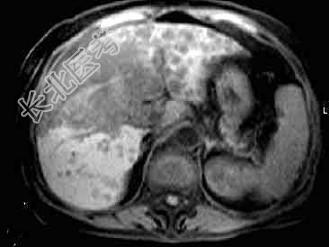

- 单项选择题根据所提供的图像,最可能的诊断是 ( )

A、胆管结石

B、肝癌

C、肝内多发囊肿

D、肝硬化

E、以上都不是